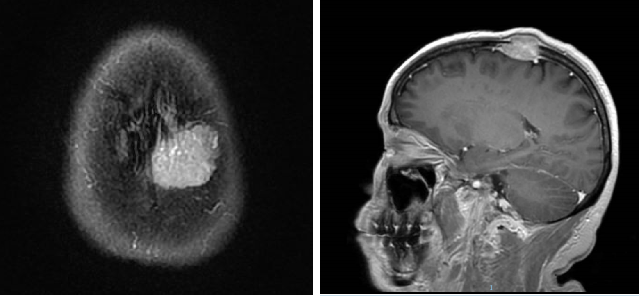

图1